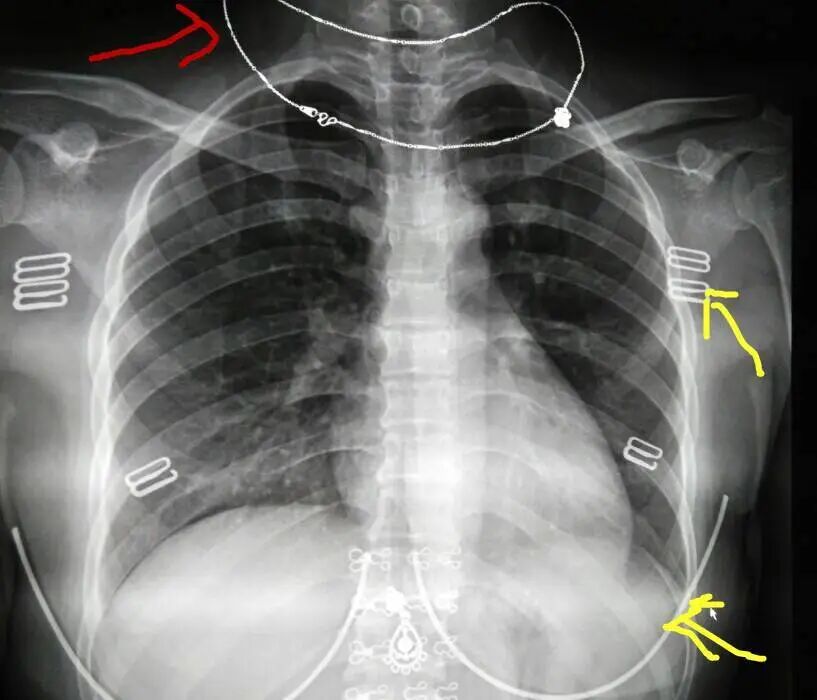

不合格胸片赏析

DR胶片为什么分尺寸借DR成像原理详解胸部正位摄片技术参数_https://www.jmylbn.com_新闻资讯_第8张

缺陷:两肩胛骨未拉开肺野之外,吸气不完全,且存在金属饰品遮挡。

解决:去除金属饰品及内衣后重新按标准体位摄片即可。